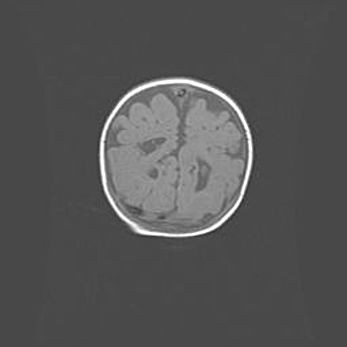

Открытая гидроцефалия.

Возраст: 6 месяцев 15 дней

Вес: 6200 г

Пол: женский

Окружность головы: 41 см

Срок гестации: 38 недель

Гидроцефалия головного мозга у новорожденных – это скопление избыточного количества цереброспинальной жидкости в головном мозге. Ее избыточное скопление в мозге приводит к патологическому расширению желудочков мозга (четырех полостей, расположенных в глубине белого вещества мозга, заполненных цереброспинальной жидкостью и связанных узкими проходами).

Открытый тип гидроцефалии (сообщающаяся) наблюдается тогда, когда нарушен механизм всасывания ликвора в системный кровоток. При этом типе причиной заболевания чаще всего является перенесенные ранее инфекции (например: менингит),  либо же наличие крови в субарахноидальном пространстве.